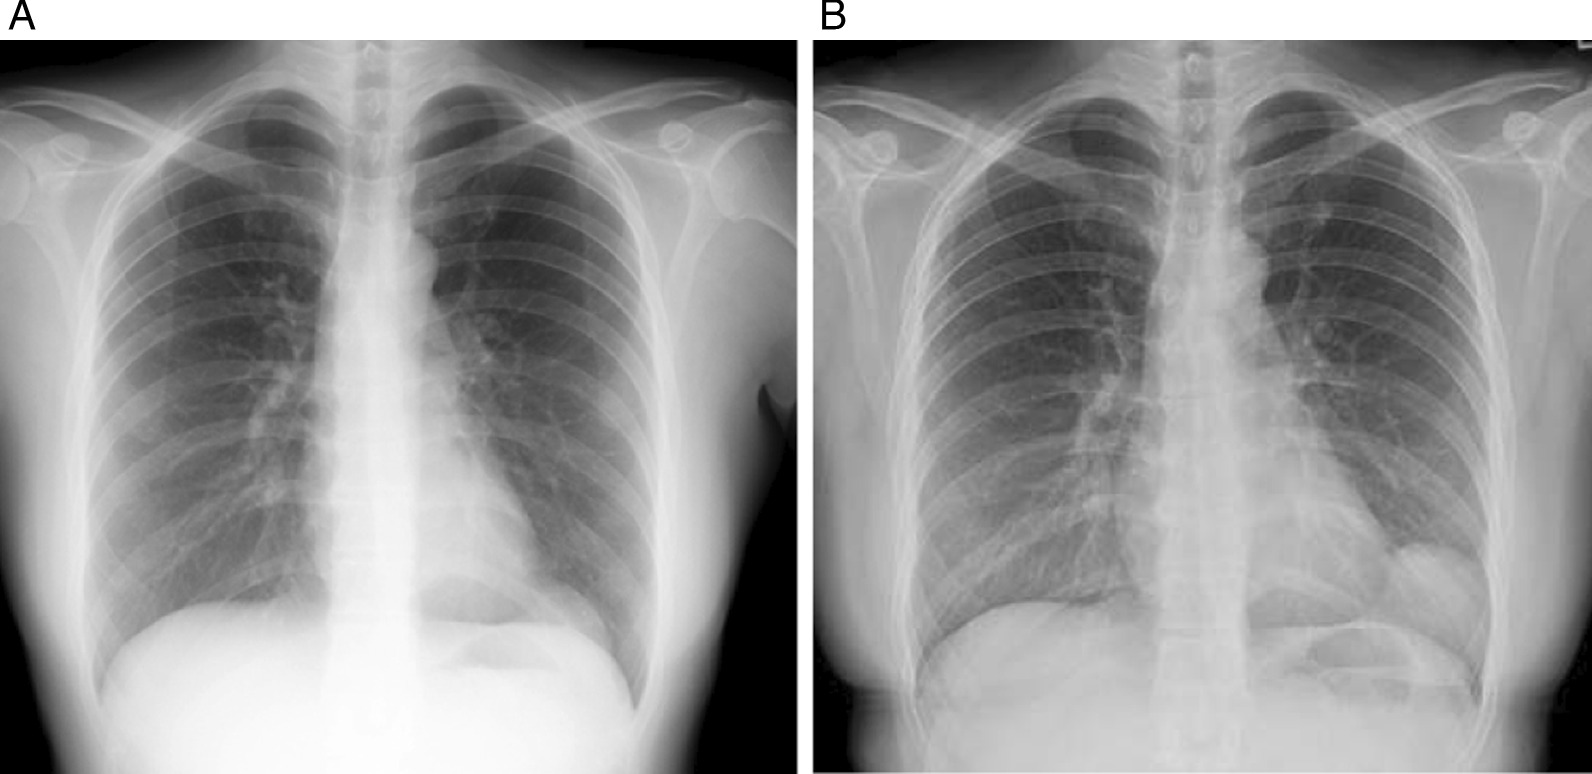

A 32-year-old Asian female visited us for examination of an abnormality on her chest X-ray. There was a well-defined mass lesion around the apex of the heart. The mass had developed and grown within 1 year (Fig. 1A, B). The tumor size enlarged from 34 to 64 mm in the largest diameter by chest X-ray. The patient was asymptomatic, had never smoked, and had a history of hyperthyroidism treated with thiamazole. However, she was medication-free on admission to our hospital. She had no history of pregnancy and no history of childbirth. There was no remarkable family history of illness, including cancer. She is a desk worker with no history of exposure to certain chemicals or asbestos. Her vital signs, physical examination, and neurological examination on admission were unremarkable. Her laboratory finding was within the standard limit on blood cell counts, liver and renal functions, urinalysis, and other serology. Chest computed tomography (CT) revealed a pear-shaped mass lesion measuring 80 mm in the largest diameter that had developed between the pericardium and the left lung (Fig. 2). The lesion was monotonous and had a computed tomography value between 23 and 32 HU. It was growing expansively and did not seem to invade the adjacent organs. The lesion showed a low signal on T1-weighted magnetic resonance imaging (MRI) and a low and heterogeneous signal on T2-weighted fat-saturation imaging (Fig. 3A, B).

Fig. 1.

Chest X-ray taken in A 2018 and B 2019. The tumor size enlarged from 34 to 64 mm in the largest diameter